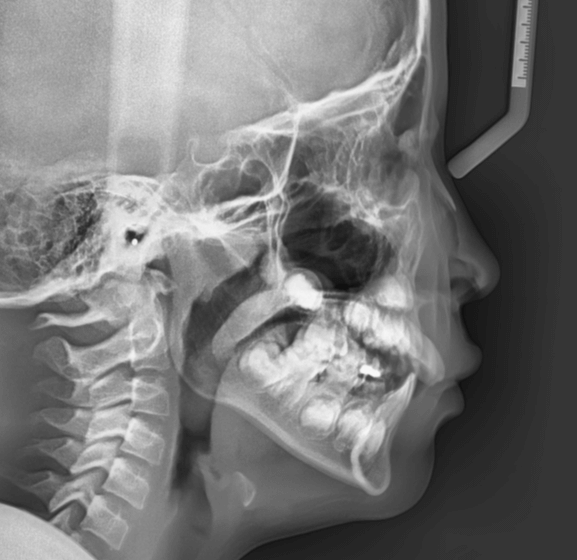

STEP2 精密検査

カウンセリング後、本格的に治療を進めるために精密検査に移ります。より詳しい口腔内の検査、顔・口内の写真撮影、レントゲンやCT撮影、歯型取りが具体的な内容です。顎の骨の歪みをはじめ、骨格的な問題が無いかも診察します。

診断結果 | 8歳7か月の男児 前歯の反対咬合(下顎前突)診断 |

治療内容 |

|

治療後の経過 | 動的治療は1年3か月で完了。反対咬合は改善されました。現在は3〜4か月ごとの定期検診で経過観察中で、今後本格的な矯正治療へ移行予定です。 |

治療期間 | 動的治療期間:1年3か月 治療回数:11回 |

治療費用 | 400,000円(税別) |